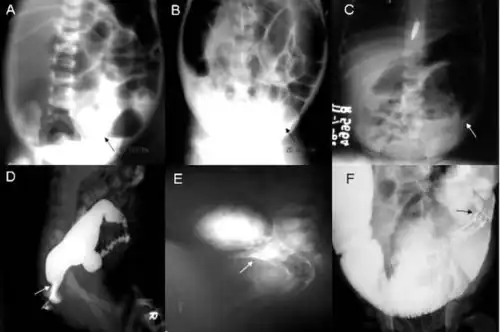

Badanie radiologiczne

Przeglądowe zdjęcie rtg w pozycji wiszącej

Na zdjęciu stwierdza się charakterystyczny obraz rozdętych pętli jelitowych z poziomami płynu, typowy dla niskiej niedrożności przewodu pokarmowego. Niestale obserwuje się niewielka ilość gazu w bezzwojowym odcinku jelita. W przypadku perforacji obecne jest powietrze pod kopułą przepony.

Wlew stosuje się na nieczyszczone jelito; wcześniejsza lewatywa albo badanie per rectum utrudnia interpretację wyniku. Typowo środek kontrastowy uwidacznia wąski segment bezzwojowy i proksymalnie do niego poszerzony odcinek prawidłowy. Przeciwwskazaniem do tego badania jest obecność objawów stanu zapalnego jelita cienkiego i grubego.

Badanie wykonuje się po ukończeniu 12 dni życia, ponieważ do tego czasu odruch relaksacyjny zwieracza zewnętrznego może być niewykształcony[85]. Brak zwiotczenia zwieracza lub paradoksalny wzrost napięcia w odpowiedzi na wzrost ciśnienia w bańce odbytnicy wskazuje na rozpoznanie choroby Hirschsprunga.